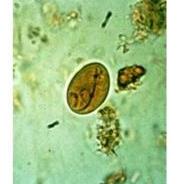

Apacor Odczynniki do analiz parazytologicznych

Odczynniki do analiz parazytologicznych